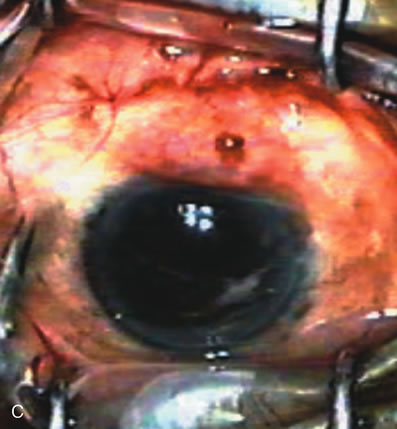

Fig. 7. Phacotrabeculectomy adjacent to a failed filter in cataractous eye. The ability to combine small-incision cataract extraction with trabeculectomy all through the same incision adjacent to the failed filter allows the surgeon to work in a familiar superior area. Avoiding incisions into the existing bleb decreases conjunctival buttonholes, hypotony, operating room time, and subconjunctival bleeding. A. Appearance of failed bleb with exposure of superior temporal quadrant gained with a corneal traction suture. B. Prepare a limbus-based conjunctival flap and a scleral flap. C. This bleb is at high risk to fail again justifying the need for MMC, 0.2 mg/cc applied on a pledget for 4 minutes. D. Insert the keratome and perform phacotrabeculectomy in the usual fashion.